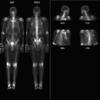

Nl Nuc Med

Date: 03/23/2004

Views: 4642